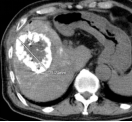

社会快速发展所带来的环境影响,让肿瘤离我们越来越近,当身边的人患有这种疾病时,给患者和亲人带来沉重的思想包袱,而开刀、化疗、放疗等传统治疗方式又给肉体带来更加痛苦的深层次打击。 患者往往对传统治疗望而却步,在绝望中等待生命的终结…… 问 还有希望吗!还有别的治疗方法吗? 答 有!而且还很易于接受。 一根细针,一根细细的PVC导管,或许就能给你带来希望。 通过细针,经皮穿刺病灶,取得细胞学、组织学等资料,可以让我们了解到底是恶性肿瘤还是良性疾病,并知道是什么类型的肿瘤;通过细针,可以让针尖加热,把肿瘤加热失去活性,就像把鸡蛋煮熟了再也孵不出小鸡那样,肿瘤就不再生长,而逐渐吸收变小;通过细针,可以把小小的粒子植入肿瘤,通过粒子缓慢释放能量,把肿瘤灭活,达到治愈肿瘤病灶的目的。 通过导管,进行血管造影进一步确认到底是不是恶性肿瘤;通过导管,并可把载有抗肿瘤药物微球直接注射进入肿瘤血管,缓慢持续长时间杀灭肿瘤细胞;通过导管,可以把给肿瘤供血的血管堵起来,让肿瘤失去血流,失去养料供给,饿死它。 上帝为你关上一扇门的同时,必定会为你打开了另一扇窗,快速发展的社会,科技日新月异,新技术新方法也给肿瘤治疗带来了新的希望。 近年来,淄博市中医医院介入科引入诸多新时代发展带来的前沿新技术,结合数千年古老神秘的中医调理,给诸多患者带来了新的希望和愉快的新生活。 病例一 2015.9 2015.9.11微波消融后 2017.4 肝动脉栓塞并粒子植入,病变直径75mm 2021.4.复查,病变直径35x23mm 病例二 2015.7 肝动脉栓塞并肝癌微波消融 2017.8 MRI复查,病变未见进展 2021.7 CT复查病灶显著缩小 患者后期按时复查,其他处有新增病灶,通过多次介入治疗,至今健在。 介入放射学 是在现代影像学(DSA、CT、超声、磁共振等)方法的引导下,采取经皮穿刺、插管,对患者进行血管造影、采集病理学、生理学、细胞学、生化学检查资料,进行药物灌注、血管栓塞或消融等"非外科手术"方法诊断和治疗多种疾病。 其特点简便、安全、有效、微创、可重复治疗和并发症少,该技术也适合肺癌、肾癌、胰腺癌、甲状腺结节、肺结节等疾病的治疗。 它将不能治疗的疾病变为可治疗、难治性疾病变为容易治疗、复杂治疗疾病变为简单治疗、大创伤治疗变为微创治疗、危险治疗疾病变为安全治疗。目前许多介入方法成为了主要的治疗方法,甚至取代或淘汰了原来的外科手术。 淄博市中医医院介入科 0533-6699127、6699128 官方微信公众号 长按关注 获取更多健康咨询 淄博市中医医院 淄博市中医医院始建于1952年,是鲁中地区最大的一所集医疗、科研、教学、养生保健四位一体的综合性三级甲等中医医院。是山东中医药大学的附属医院、国家住院医师规范化培训基地、山东省中医药预防保健服务中心。设有21个临床科室,9个医技辅助科室,开放床位700张。医院拥有核磁共振、CT等大型诊疗设备300多台件。 预约电话:0533-6699333、6433111 新院区地址:周村区新建东路1166号(碧桂园对面) 。 电话:0533-6699333、6433111 1.乘坐96路公交车到碧桂园站下车 2.乘坐291路公交车到碧桂园站下车 3.乘坐258路公交车到碧桂园站下车 老院区地址:山东省淄博市周村区新建中路75号(乘坐238路、239路、34路、96路公交车均可到达) 和平路院区地址:张店区和平路18号(南西五路与和平路转盘东北角) 电话:0533-2210092 1.乘坐35路、121路、132路、95路公交车和平小区站下车北行100米即到。 2.乘坐138路、223路公交车天星小区站下车东行200米即到。 3.乘坐96路、126路、12路公交车中国陶瓷馆站下车南行600米即到。官方抖音